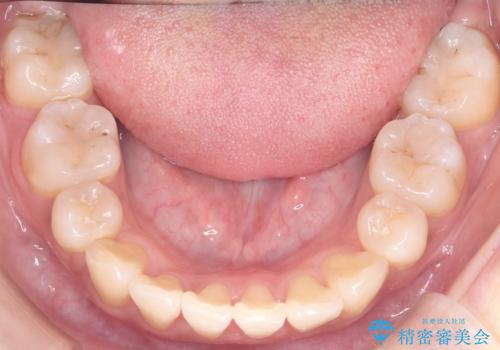

今回の矯正治療では、まず計画通り上下左右の小臼歯4本を抜歯し、八重歯や正中のズレを解消するための十分なスペースを確保しました。装置には、目立ちにくい白いブラケットとワイヤーを使用した審美ワイヤー矯正を採用。

抜歯によってできたスペースを利用し、

八重歯: 突出していた八重歯を歯列内に誘導し、デコボコを解消しました。

正中のズレ: 歯を左右対称に移動させることで、上下の歯の中心線を正確に合わせ、顔全体のバランスも改善しました。

治療の結果、長年気にされていた八重歯と正中のズレが解消し、機能的にも整った理想的な歯並びを獲得。目立たない装置で治療を完遂し、自信を持って笑える美しい笑顔を手に入れていただけました。